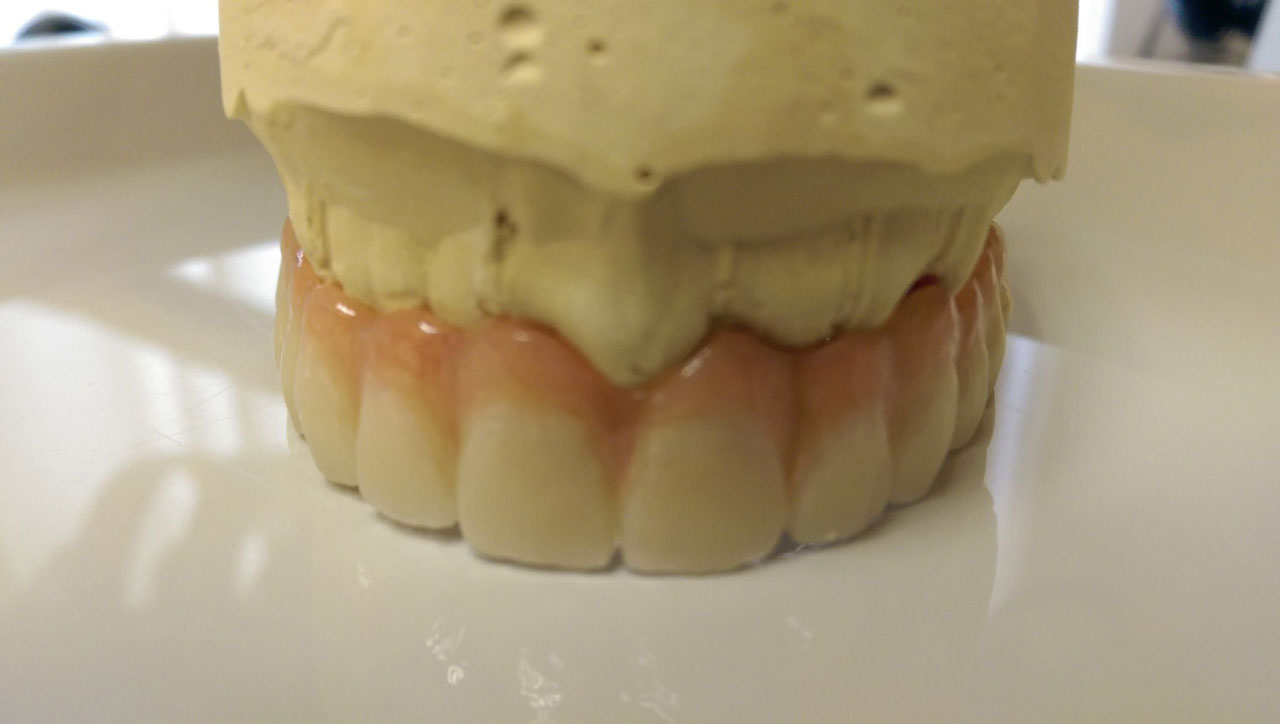

Így néz ki a hosszútávú ideiglenes híd.(Fém vázzal erősített műanyag híd.)

• esettanulmany-41

Így néz ki a hosszútávú ideiglenes híd. (Fém vázzal erősített műanyag híd.)

• esettanulmany-42